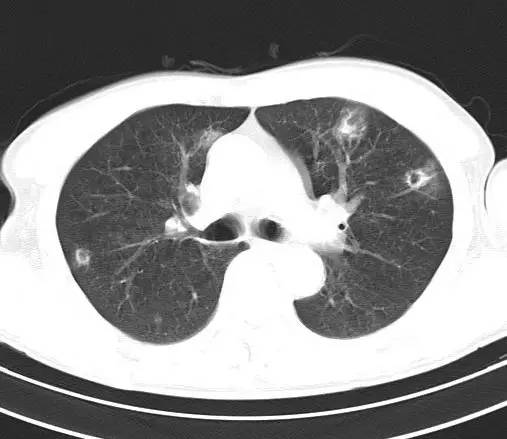

治疗前CT(图1-8):两肺胸膜下散在多发斑片状、结节状伴空洞影,边缘欠清晰。

治疗后十天CT(图9-12):双肺病灶明显缩小,有所吸收。